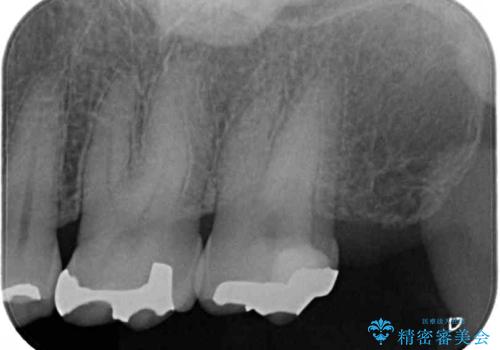

ゴールドインレーは銀歯のインレーやセラミックインレーと比べ、「技工操作の精度が高く、適合が著しく良い」というメリットがあります。特に上の奥歯は歯科医師の操作が行いにくいため、「適合の良さ」は再治療のリスクを防ぐ上でとても重要な要素となります。

上の奥歯は金属色が見えることもないため、審美的な問題は全くありません。